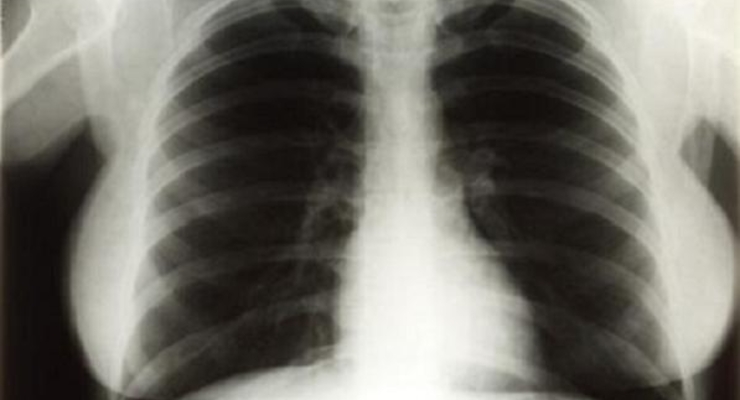

Рентгеновские снимки грудной клетки Мэрилин Монро были проданы на аукционе Hollywood Legends в Лас-Вегасе за 45 тысяч долларов.

Несколько рентгеновских снимков были сделаны в 1954 году, когда Монро поступила в медицинский центр Cedars of Lebanon Hospital во Флориде с диагнозом эндометриоз. Весной 2010 года аукционный дом Julien's объявил о том, что снимки будут проданы в рамках аукциона вещей, связанных с именами голливудских актрис. Ожидалось, что максимальная стоимость рентгена грудной клетки Мэрили Монро не превысит трех тысяч долларов.